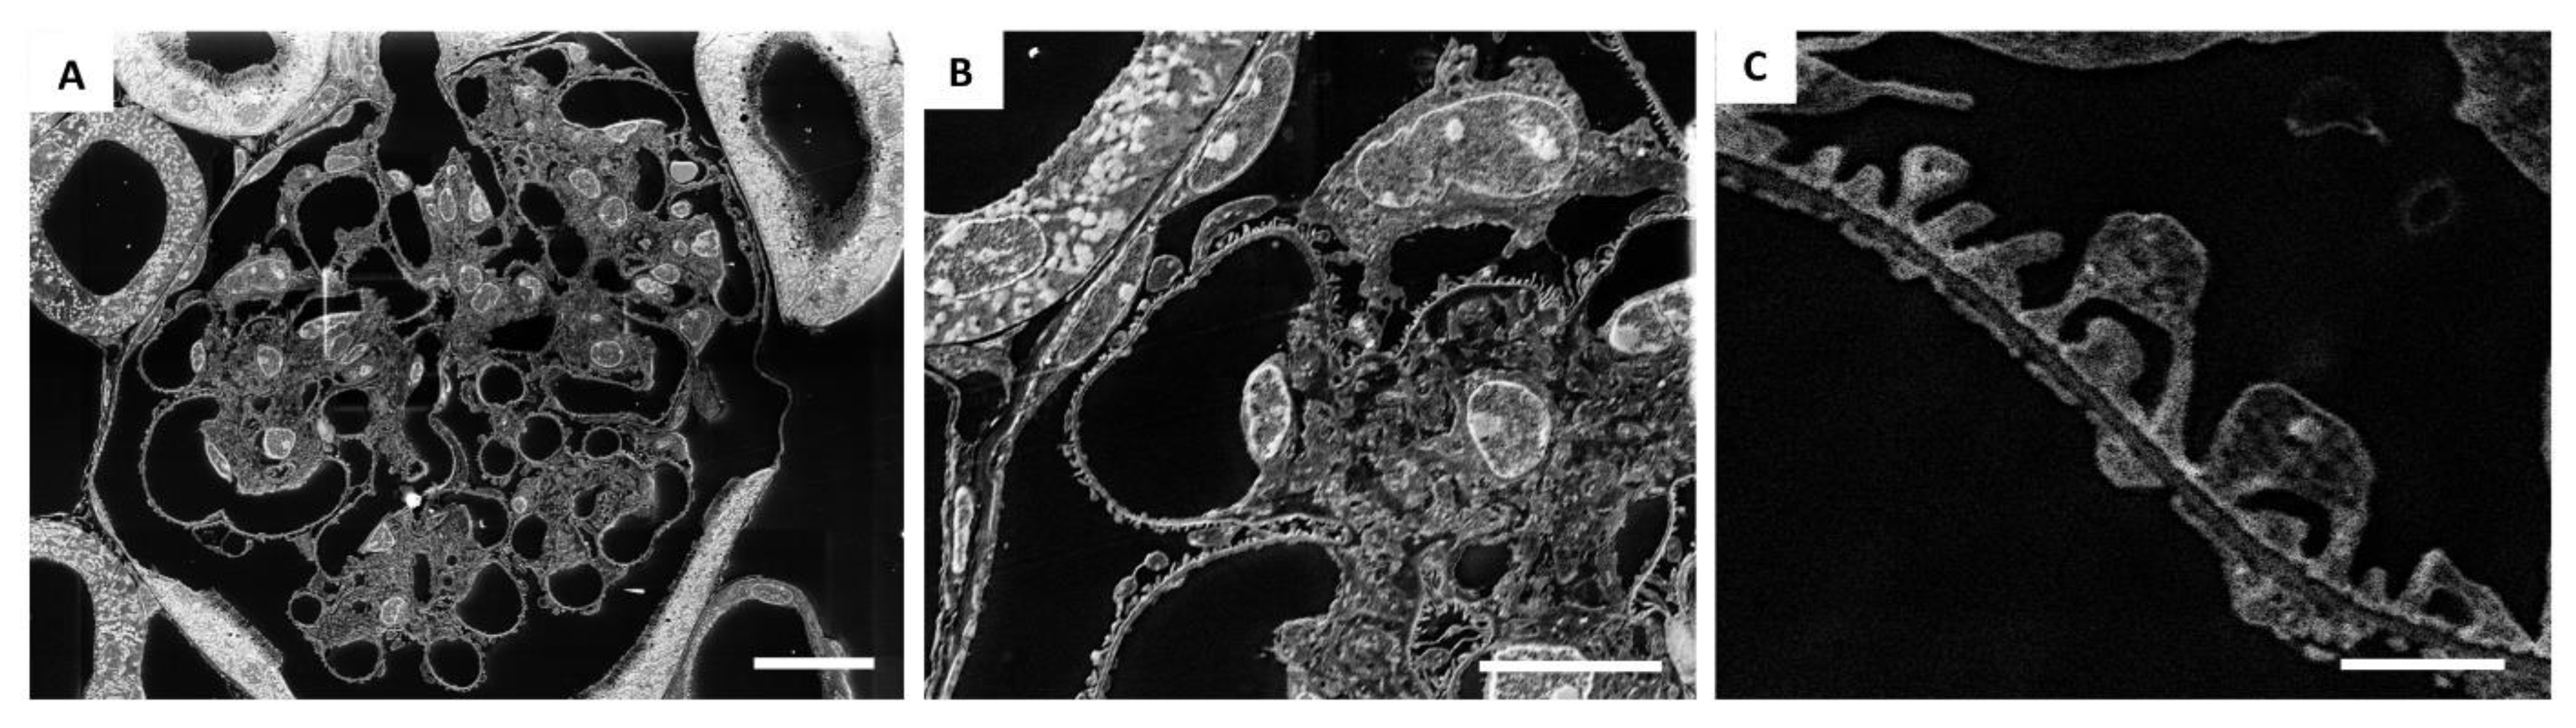

2.1. TEM-like Images from Resin-Embedded Semi-Thin Sections Using SE–SEM